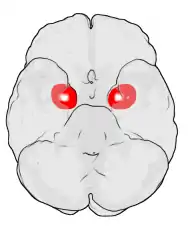

![]() Location of the amygdalae in the human brain | |

The amygdala (/əˈmɪɡdələ/; pl.: amygdalae /əˈmɪɡdəli, -laɪ/ or amygdalas; also corpus amygdaloideum; Latin from Greek, ἀμυγδαλή, amygdalē, 'almond', 'tonsil'[1]) is a paired nuclear complex present in the cerebral hemispheres of vertebrates. It is considered part of the limbic system.[2] In primates, it is located medially within the temporal lobes.[3] It consists of many nuclei, each made up of further subnuclei. The subdivision most commonly made is into the basolateral, central, cortical, and medial nuclei together with the intercalated cell clusters.[4] The amygdala has a primary role in the processing of memory, decision-making, and emotional responses (including fear, anxiety, and aggression). The amygdala was first identified and named by Karl Friedrich Burdach in 1822.[5]

Frontal and side view of amygdala

Dorsal view of the amygdalae in an average human brain

Frontal view of the amygdalae in an average human brain